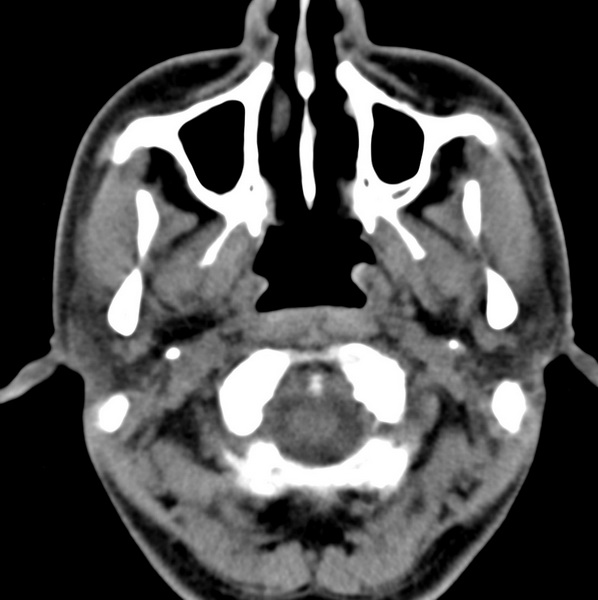

男、31、鼻咽部肿瘤放疗后请帮忙看看。

效果好,右侧破裂孔扩大,局部骨质缺损,为颅底骨质破坏。

1)鼻咽部肿瘤侵犯颅底放疗术后改变。2)左侧蝶窦炎。

咽后壁增厚,左侧咽鼓管隆突增大、咽鼓管咽口变浅,同侧咽旁间隙较窄。右侧颅底骨质破坏?为什么不在同一侧?

鼻咽部肿瘤侵犯颅底放疗术后改变.